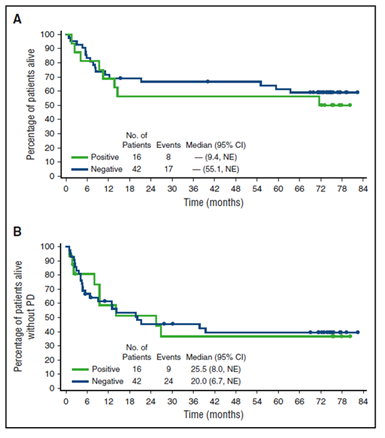

En la actualización de 5 años de Pro et al. las respuestas globales de acuerdo al investigador fueron del 86% y las RC del 66%, (Tabla 2)(15). La duración de respuesta obtenida al BV fue independiente del estatus de ALK (Figura 6).

Figura 6. SG y SLP según el estatus de ALK

En los pacientes con RC (38 de 58, 66%) la SLP para los que recibieron como consolidación un trasplante fue mejor en comparación con los pacientes sin trasplante (69% vs. 48%) aunque aproximadamente la mitad de estos últimos lograron control de la enfermedad a largo plazo (Figura 6). Los pacientes que lograron RC con BV presentaron tasas de SG y SLP del 79% y 57% respectivamente con una mediana de duración de respuesta y SG no alcanzada. Aproximadamente el 91% de los pacientes que experimentaron neuropatía periférica con BV tuvieron resolución o mejoría de los síntomas.

Figura 7. SLP según estatus de TCPH

Entre los 38 pacientes que lograron RC, 16 se sometieron como consolidación a un trasplante de células hematopoyéticas. Entre estos 16 pacientes que recibieron un trasplante, los resultados a los 5 años fueron similares entre los pacientes que se sometieron a un trasplante autólogo en comparación con los pacientes que recibieron trasplante alogénico. De los 8 pacientes que recibieron un trasplante alogénico, 6 se habían sometido a un trasplante autólogo previo al ingreso al estudio. La mediana de SLP para los 22 pacientes que no procedieron al trasplante fue 39,4 meses con una tasa de SLP a 5 años del 48% (Figura 7). De los 22 pacientes que no recibieron SCT, 12 (54%) estaban vivos sin enfermedad progresiva en último seguimiento y la tasa de SG a 5 años fue del 81% con una mediana no alcanzada aún, evidenciado que es posible tener una posibilidad de control a largo plazo e incluso de estos pacientes que antaño eran de muy mal pronóstico. Incluso algunos expertos hablan de la posibilidad de cura(16).